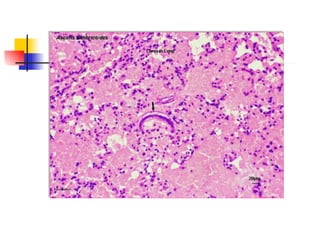

PULMON Migración larvaria Ruptura de alvéolos Hemorragia Exudado inflamatorio Moco Reacción granulomatosa PATOLOGÍA

Larva de A.lumbricoides en pulmón

PULMON Migración larvariaRuptura de alvéolos Hemorragia Exudado inflamatorio Moco Reacción granulomatosa PATOLOGÍA